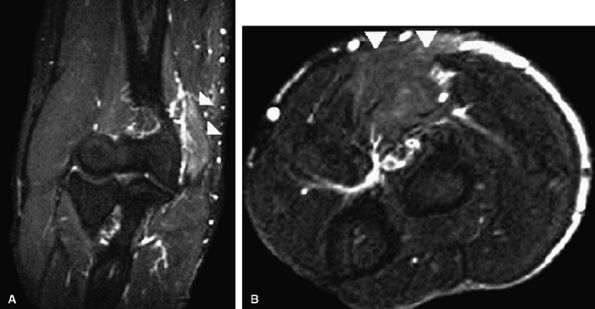

On MR examinations obtained after anterior ulnar nerve transposition, T2 hyperintensity equalize within the ulnar nerve may persist long after the surgery (Fig. 12.27). Intense increased signal, however, is more likely to reflect persistent neuritis. Ulnar nerve thickening can be seen in the first postoperative year in up to 50% of patients following transposition.65 Tethering of the nerve and engulfing scar can also be identified. Other causes

P.1957

for persistent pain after anterior ulnar nerve transposition include extensive scarring or retearing at the resection site of the pronator–flexor muscle group.

FIGURE 12.27 ● Failed anterior ulnar nerve transposition. Axial post-contrast fat-suppressed T1-weighted image (A) and oblique sagittal fat-suppressed T2-weighted image (B) demonstrate increased signal and thickening of the transferred ulnar nerve (arrowheads). m, medial epicondyle.

|